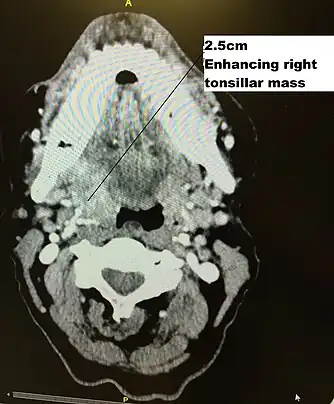

CT scan in transverse plane, viewed from below, showing a contrast enhancing right tonsil mass due to HPV+OPC

HPV+OPC is usually diagnosed at a more advanced stage than HPV-OPC,[8] with 75–90% having involvement of regional lymph nodes.[52] Furthermore, HPV+OPC is more likely to be poorly differentiated with nonkeratinized or basaloid cells.[53][54] [51]